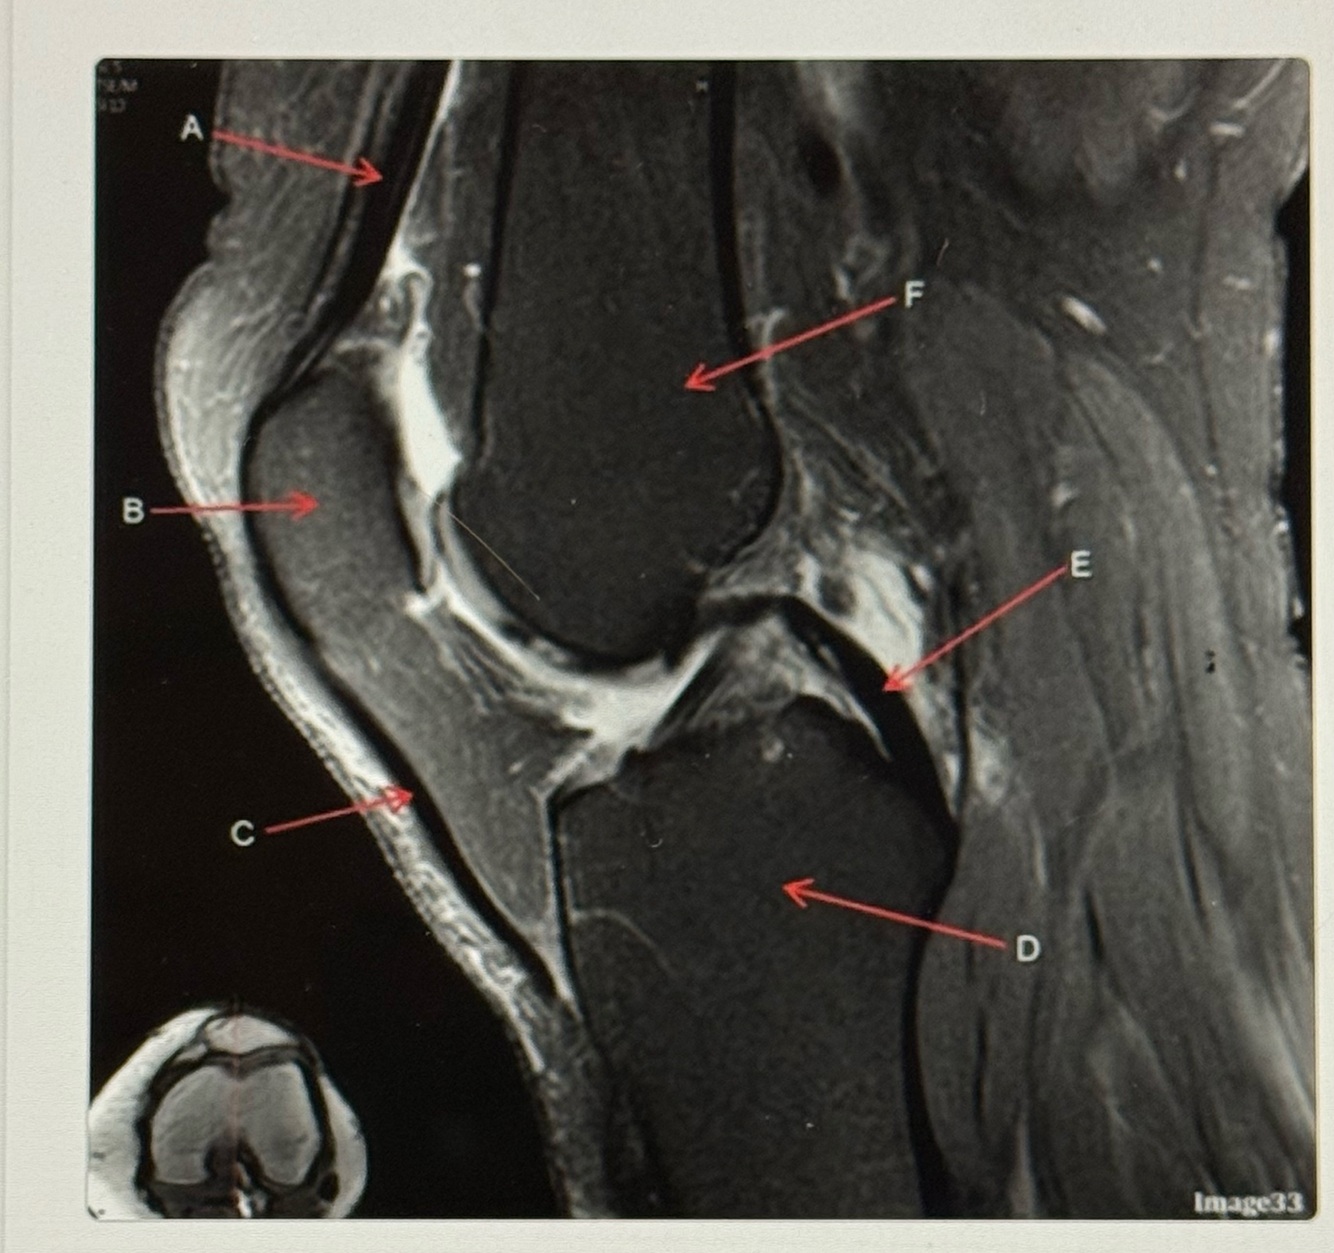

10

Q

Letter B points to the

A

Femur

11

Letter A points to the

Patella

12

Letter C points to the

Anterior horn of lateral meniscus

13

Letter D points to the

Tibia

14

Letter E points to the

Head of the fibula

15

Letter F points to the

Posterior horn of the lateral meniscus

16

Patellar tendon

17

18

Posterior cruciate ligament (PCL)

19